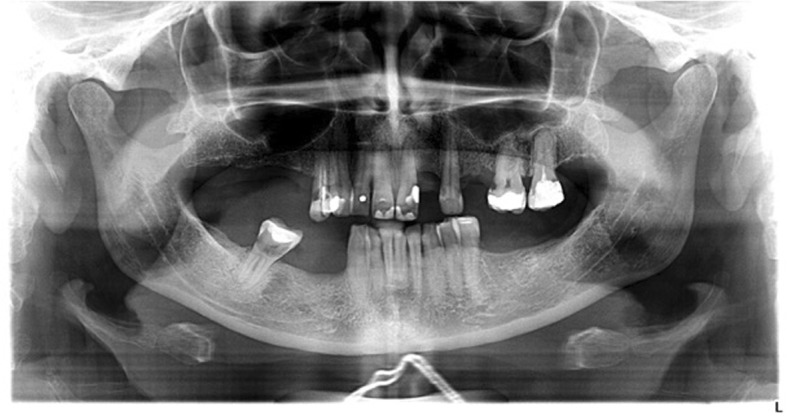

Moreover, a morphological classification of the mandibular cortical bone has been proceeded on panoramic radiographs. Mandibular cortical index (MCI) according to Klemetti et al. [20] was used to assess morphological changes in the inferior cortex of the mandible. Mandibular cortical shapes were analysed by observing the mandible distally from the mental foramina bilaterally and by categorizing them into one of the following three groups as previously described by Klemetti et al. [20]: “C1 – the endosteal margin of the cortex is even and sharp on both sides (Fig. 2); C2 - the endosteal margin shows semilunar defects (lacunar resorption) or endosteal cortical residues on one or both sides, mild to moderate cortex erosion (Fig. 3); C3 – the cortical layer forms heavy endosteal cortical residues and clearly porous, severely eroded cortex” (Fig. 4).

Fig. 2.

Panoramic radiograph with C1 category of MCI